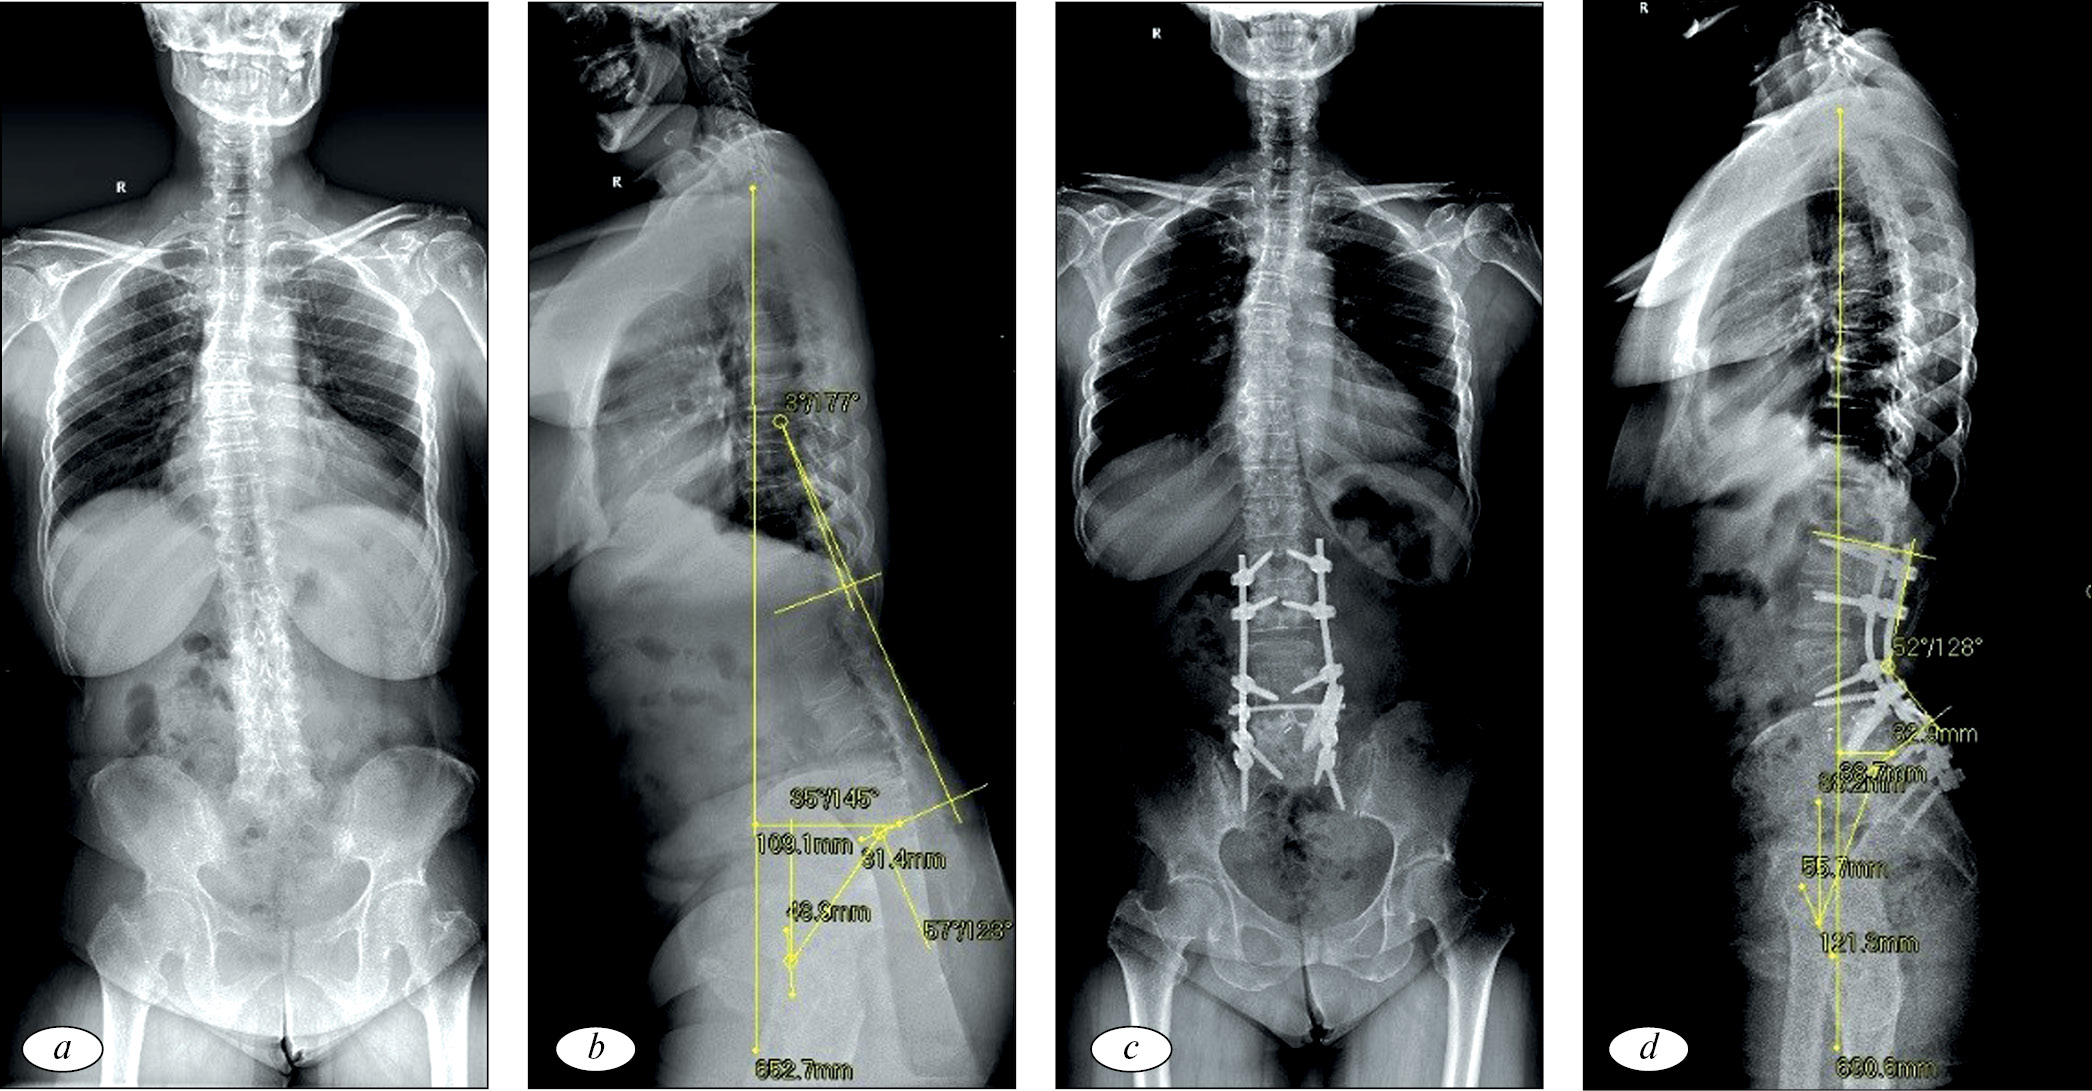

На рис. 1 и 2 представлены клинические примеры хирургического лечения пациентов из группы PSO и комбинированного лечения.

Рис. 2. Рентгенограммы пациентки, 50 лет, с поясничным сколиозом de novo, нарушением сагиттального баланса, дегенеративным стенозом, проявляющихся выраженным болевым синдромом в поясничном отделе позвоночника и нейрогенной перемежающейся хромотой: a и b — дооперационные рентгенограммы в степ-режиме в боковой и прямой проекциях. PI — 46°, PI-LL — 26°, PT — 18°, SVA — 78 мм, LDI — 96 %, GAP — 7 баллов, III тип Russouly. Пациентке проведено: ALIF на уровнях L4-L5, L5-S1 и DLIF на уровнях L2-L3, L4-L5, остеотомия Schwab I и II тип на всех уровнях, задняя винтовая фиксация L2-S1; с и d (через 1 год) — рентгенограммы в степ-режиме в боковой и прямой проекциях после. PI — 46°, PI-LL — 3°, PT — 13°, SVA — 30 мм, LDI — 79 %, GAP — 2 балла